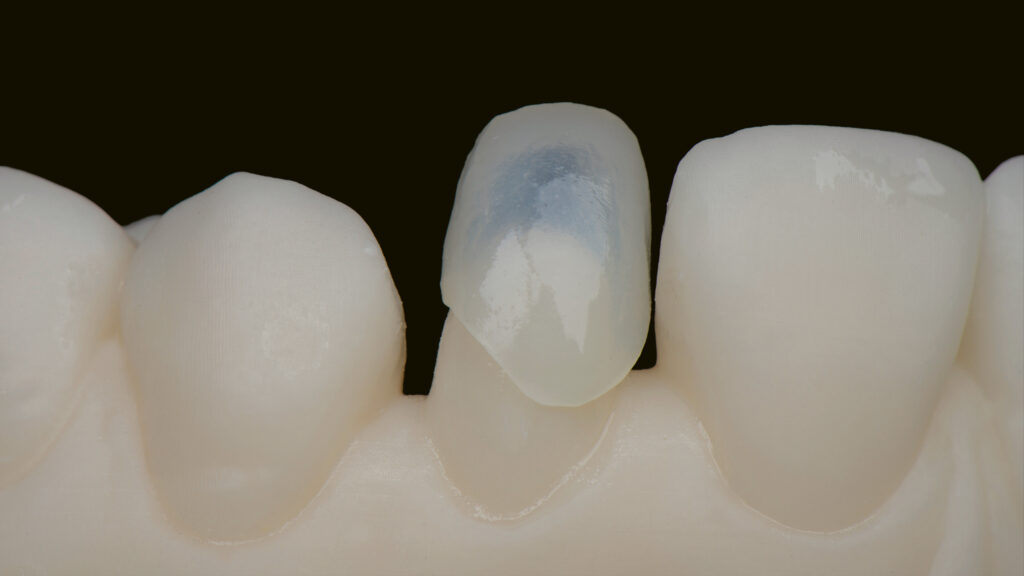

Vita Ambria (Vita Zahnfabrik, Bad Säckingen) ist ein mit Zirkonoxid verstärktes Lithiumdisilikat mit hoher Festigkeit (>500 Mpa), das in der Presstechnik verarbeitet wird. Die Keramik eignet sich besonders für die effiziente Herstellung von hochästhetischen, langlebigen Restaurationen wie Overlays und Teilkronen. Das Presskeramik-System enthält Presspellets in den Transluzenzstufen T (transluzent) und HT (hochtransluzent) (Abb. 15). Ein Vorteil ist, dass die aus Vita Ambria gepresste Restauration vollanatomisch und monolithisch bemalt und glasiert oder mit der Verblendkeramik Vita Lumex AC (Vita Zahnfabrik) fertiggestellt werden kann. Nach dem Modellieren des hauchdünnen Käppchens (Abb. 16) und dem Pressen erfolgt das Ausbetten der Keramikschale. Die minimale Reaktionsschicht kann mit geringem Druck (2 bar) abgestrahlt werden, so dass passgenaue Ergebnisse effizient erzielt werden. Da die Schale in der Farbe A1 (HT-Rohling) gepresst wurde (Abb. 17) und die Schichtstärke nur 0,2 bis 0,3 mm beträgt, wirkt sie sehr transluzent (Abb. 18). Es folgt die Verblendung mit Vita Lumex AC. Hier zeigt sich ein weiterer Vorteil für die Umsetzung dieses Falles. Denn die Verblendkeramik kann auch auf Zirkonoxidgerüsten verwendet werden. Vita Lumex AC ist eine leutzitverstärkte Glaskeramik zur Verblendung vollkeramischer Gerüste aus Zirkondioxid-, Lithiumdisilikat- und Feldspatkeramik sowie zur Herstellung von keramischen Veneers.

Individuelle Minimal-Schichtung

Vor dem Brand wird etwas „Smoky White“ auf das Käppchen gestreut, um den Helligkeitswert zu erhöhen (Abb. 19). Eine Aufnahme unter UV-Licht verdeutlicht die Fluoreszenz der gestreuten Keramikmasse (Abb. 20). Die Vorteile der Streutechnik sind keine Erfindung von uns. Vielmehr hat uns unser Kollege und Freund Oliver Brix darauf hingewiesen, wie solche Käppchen vorbehandelt werden können, um eine bessere Tiefenwirkung zu erzielen. Für den ersten Hauptbrand wird interdental/zervikal eine dünne Schicht Effekt-Chroma aufgetragen und die anatomische Form mit etwas Dentin A1 ergänzt. Nach einem Cutback (Abb. 21) des inzisalen Drittels wird eine Mischung aus Schneidemasse sowie „Light“- und „Waterdrop“-Masse (tranzluzente blau/graue Masse) im Verhältnis 1:1 als Schneideteller aufgebaut (Abb. 22). Auf Opakdentin wurde aus Platzgründen und zur besseren Sichtbarkeit der natürlichen Zahnfarbe verzichtet. Die dünne Kappe bietet genügend Transluzenz und Helligkeit, um mit einer dünnen Schicht Verblendkeramik die gewünschte Helligkeit, Sättigung und Farbe zu erzielen. Die Individualisierung der Inzisalkante erfolgt mit der wärmeren und fluoreszierenden Keramik „Saffron“, die mit Interno Liquid angemischt wird (Abb. 23). Vorteil dieser Mischung ist, dass das Liquid die Masse besser einfärbt und so die Sättigung mit bloßem Auge kontrolliert werden kann. Außerdem ist die angemischte Masse sehr plastisch und lässt sich kontrolliert auf den Inzisalteller auftragen. Zur Imitation von weißlichen Kalkflecken wird „Smoky White“ mit Interno Liquid angemischt und mit dem Pinsel in die Schneidemasse eingearbeitet (Abb. 24). Nach dem ersten Brand der minimalen Schichtung sind alle Merkmale gut sichtbar. Wie in der Natur kommen sie aus der Tiefe (Abb. 25 bis 27).

Beim zweiten Brand wird die minimale Schichtung mit „Tranzluzent Clear“ ergänzt, um eine Art Filtereffekt zu erzeugen. Dies simuliert einen 3D-Effekt (Envelope-Technik), der feine Details aus der Tiefe erscheinen lässt. Der distale Kontaktpunkt wird mit etwas Dentin aufgebaut (Abb. 28). Das Gerüst wurde aus einem HT-Rohling gepresst, um einen Chamäleoneffekt zu erzielen. Dies ist mit transparenten Massen gut möglich. Dieses Vorgehen sollte jedoch nur dann gewählt werden, wenn keine Farbveränderungen (z. B. bei verfärbten Zähnen) gewünscht sind. Grundsätzlich erspart ein detaillierter Auftrag der Keramikmassen ein aufwendiges Beschleifen der Keramikrestauration im Nachhinein (Abb. 29).